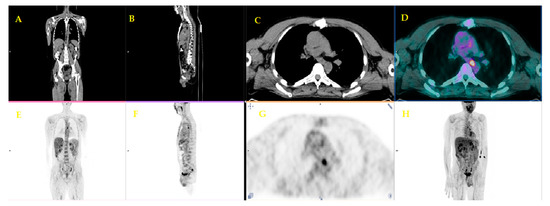

| 16 | Ghaneh et al. [31] | 2018 | Prospective study | 589 | Whole management | FDG PET/CT, in addition to standard diagnostic work-up of PDAC, correctly changed the staging of PDAC in 10% of cases, influenced the planned management in 45%, avoided un-useful resection in 20% of patients scheduled for surgery, and got a limited role in chronic pancreatitis. |